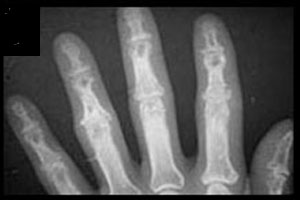

Acute polyarthritis is a common presenting symptom of sarcoidosis, but these patients do not have radiologic abnormalities. Visible bone lesions are associated with chronic disease and are rare unless the patient has skin lesions. The hands and feet are sites of lesions much more often than any other bone. The distal and middle phalanges are most often involved. The lesions are often few and inconspicuous, but rarely chronic disease leads to more severe and even destructive disease. Destructive granulomatous lesions can also occur in the facial bones and involve adjacent structures such as the paranasal sinuses, lacrimal glands, and optic nerve.

Osteolysis has left a lacy trabecular pattern in this phalanx (arrow)

Advanced sarcoidosis with numerous osteolytic lesions of the distal forearm, wrist, and bones of the hand cause gross deformity.